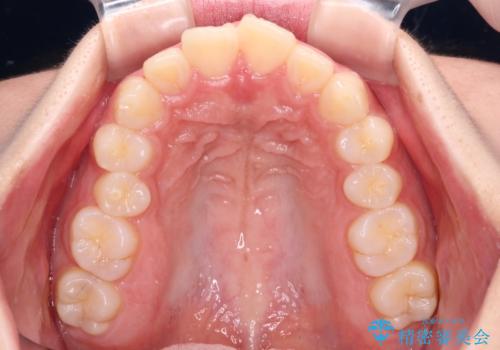

- 飛び出した上顎前歯と、閉じにくい唇、口元の突出した印象の横顔を気にして来院された患者様です。

骨格的な上顎前突であり、上下前歯の前後的な距離が大きいため、上顎は左右第一小臼歯を、下顎は左右第二小臼歯をそれぞれ2本抜歯することで前歯が接触するようにし、さらには奥歯の咬み合わせも、より理想的な状態へ近づけていくこととしました。

3年以上はかかる難症例であるため、表側のワイヤー装置にて治療を行うこととしました。

事前の予想通り、長期間を要する治療となりましたが、横顔の印象が劇的に変化し、患者様には大変満足していただきました。